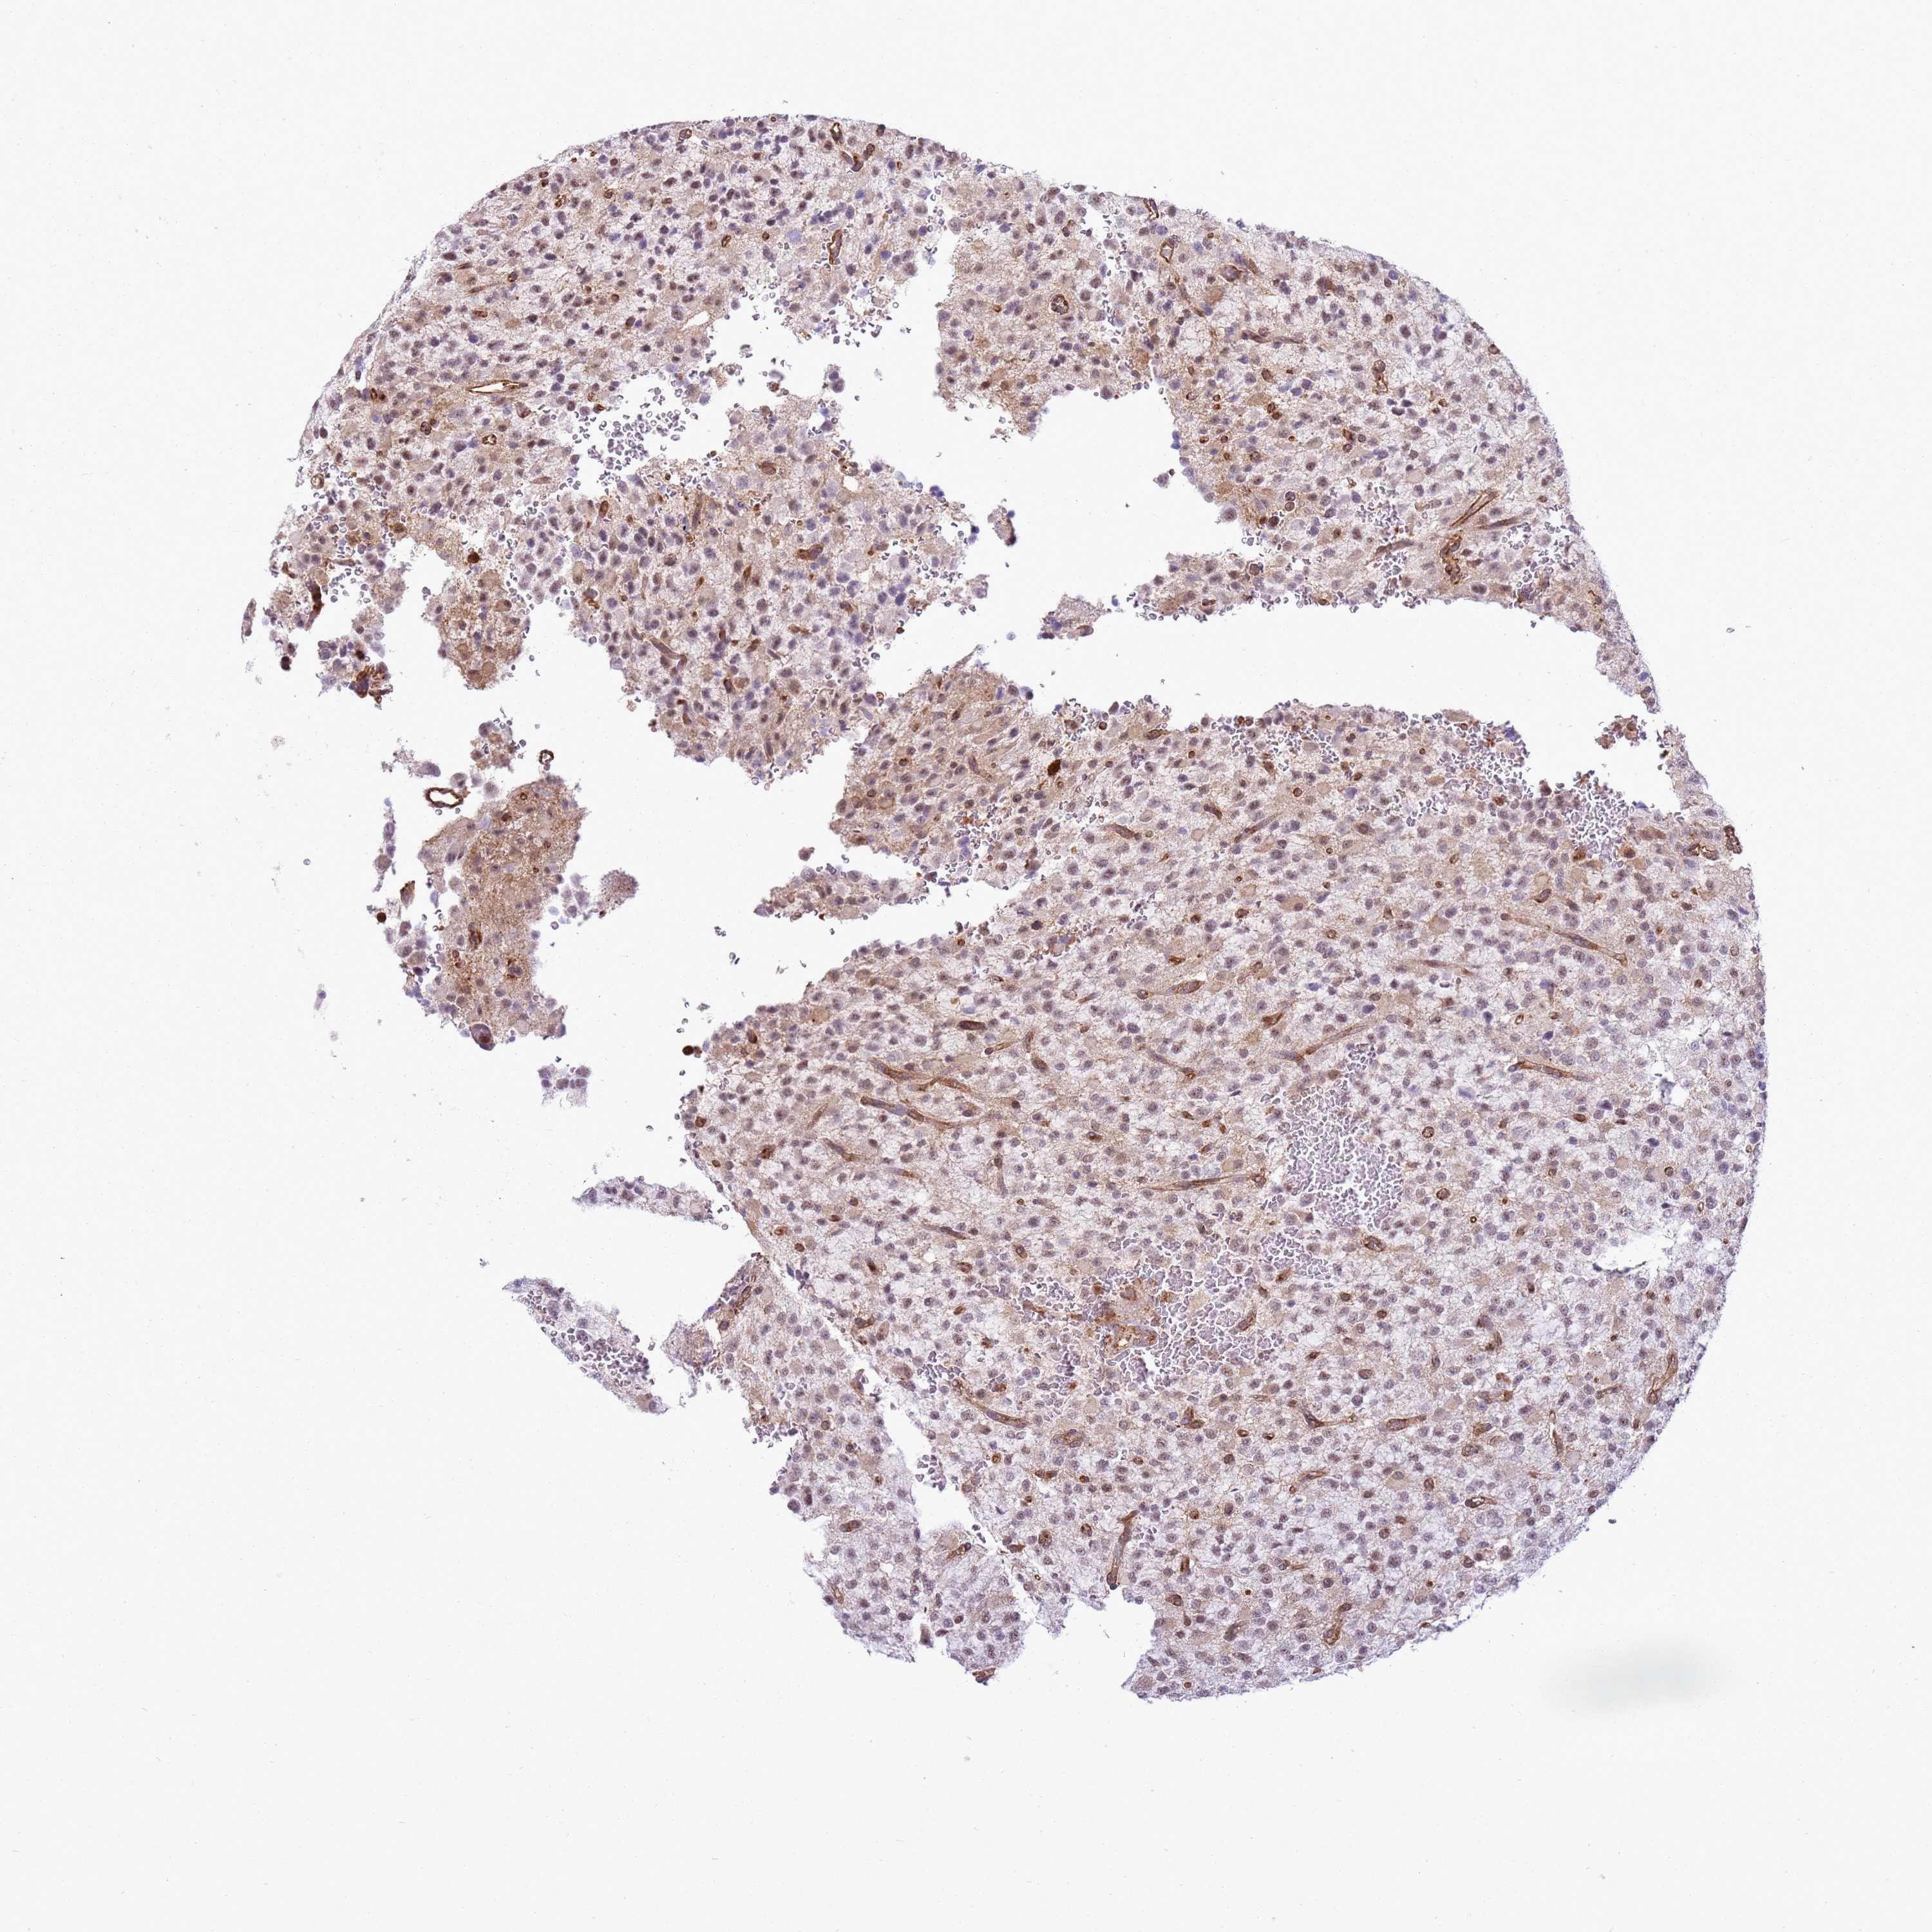

GLIOMA - Protein expressioni

A mouse-over function shows sample information and annotation data. Click on an image to view it in a full screen mode. Samples can be filtered based on level of antibody staining by selecting one or several of the following categories: high, medium, low and not detected. The assay and annotation is described here.

Note that samples used for immunohistochemistry by the Human Protein Atlas do not correspond to samples in the TCGA dataset.

Antibody stainingi

Antibody staining in the annotated cell types in the current human tissue is reported as not detected, low, medium, or high, based on conventional immunohistochemistry profiling in selected tissues. This score is based on the combination of the staining intensity and fraction of stained cells.

Each image is clickable and will lead to virtual microscopy that enables deeper exploration of all samples and also displays staining intensity scores, fraction scores and subcellular localization as well as patient and tissue information for each sample.

Antibody HPA045918

Staining

High

Medium

Low

Not detected

Intensity

Strong

Moderate

Weak

Negative

Quantity

>75%

75%-25%

<25%

None

Location

Nuclear

Cytoplasmic/membranous

Cytoplasmic/membranous,nuclear

Glioma, malignant, High grade

Glioma, malignant, Low grade

Glioblastoma, NOS